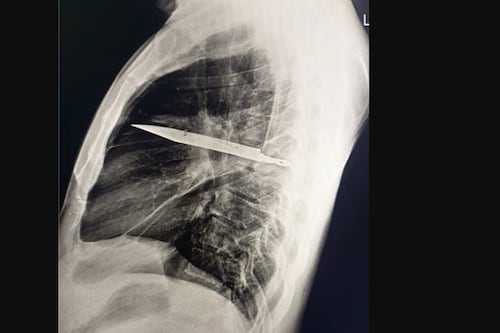

¿Un cuchillo en el pecho por 8 años? El escalofriante hallazgo médico que desafía las leyes de la biología

Un hombre convivió con un cuchillo en el tórax durante 8 años sin sentir dolor. Analizamos la ciencia detrás de este asombroso caso clínico.